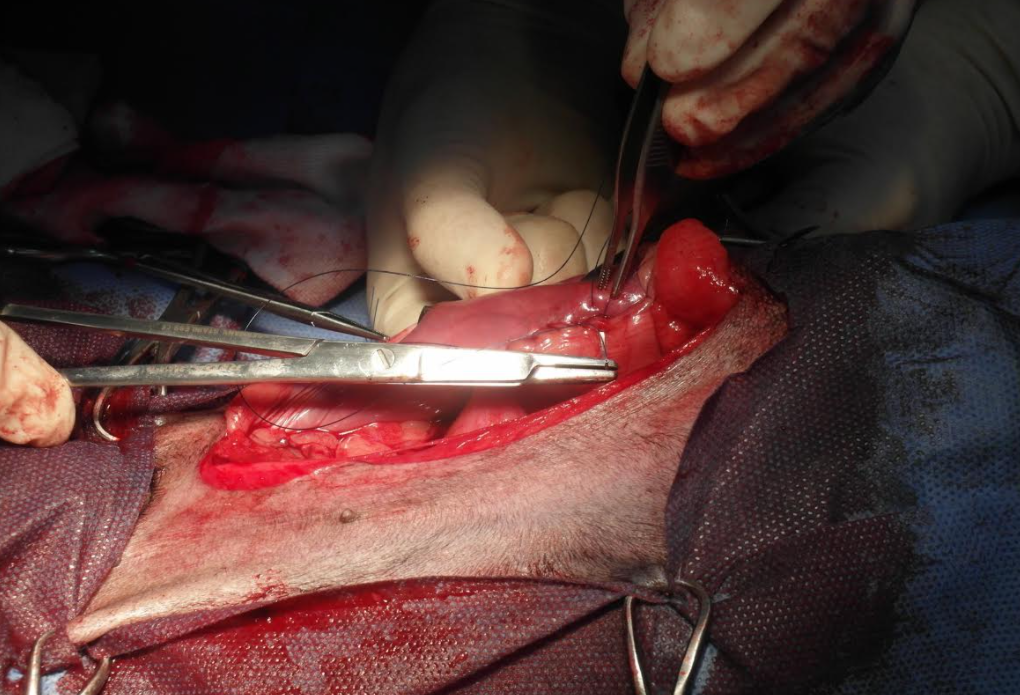

術中執行胃固定

GDV如果沒有及時把胃裡面的氣放掉,短時間內會有休克死亡的風險,因此緊急放氣處理後,開腹手術執行胃固定術,術後3-5天內需是高危險期,持續密集監控心跳、呼吸、血壓、血氧、心電圖、體溫..等等重要生理數值。住院三天後順利出院。